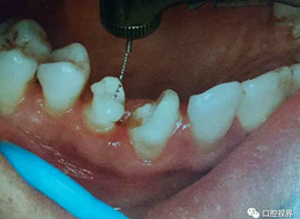

5. 牙體預(yù)備時(shí)機(jī)

纖維樁核堆塑完成后即刻行牙體預(yù)備,此時(shí)混合層未完全形成,高速手機(jī)震動(dòng)導(dǎo)致樹脂突移位斷裂,牙體預(yù)備的水霧使粘結(jié)劑吸濕膨脹。有學(xué)者建議24 h 后行牙體預(yù)備,此時(shí)混合層穩(wěn)定形成。